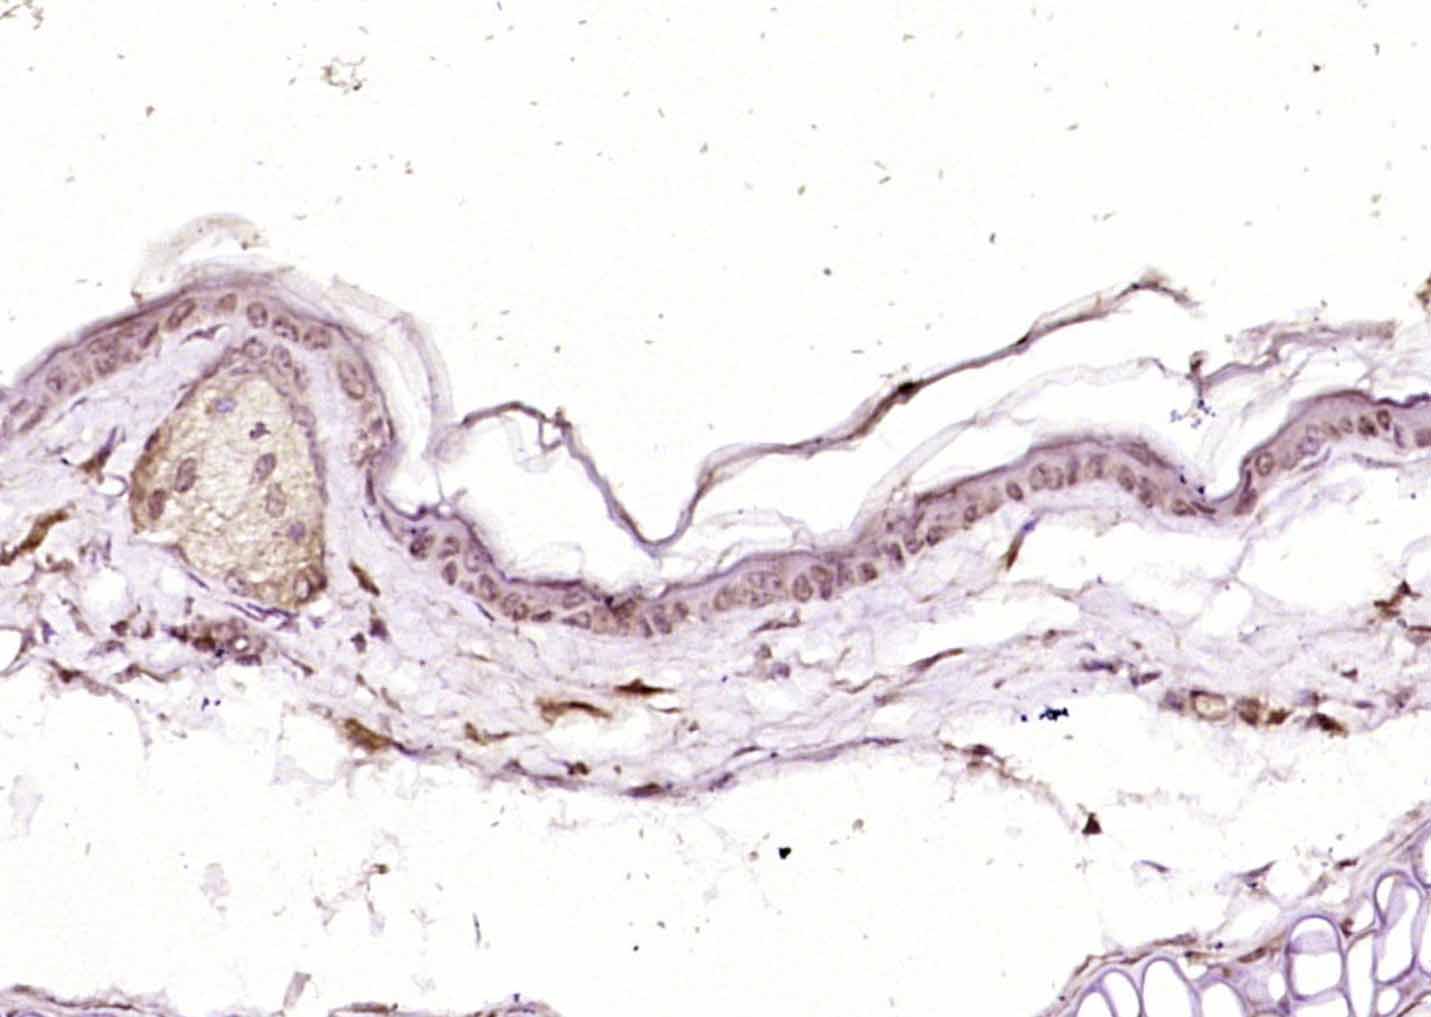

Antigen retrieval: citrate buffer ( 0.01M, pH 6.0 ), Boiling bathing for 15min; Block endogenous peroxidase by 3% Hydrogen peroxide for 30min; Blocking buffer (normal goat serum,C-0005) at 37℃ for 20 min;

Incubation: Anti-RHEB Polyclonal Antibody, Unconjugated(bs-3832R) 1:200, overnight at 4°C, followed by conjugation to the secondary antibody(SP-0023) and DAB(C-0010) staining